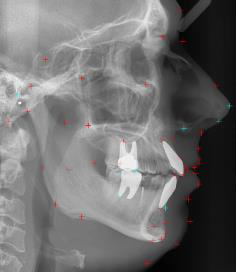

自動Ceph分析軟體